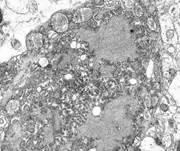

NO.1 马尔堡病毒

马尔堡病毒所到之处,寸草不生。同埃博拉病毒一样,这两种病毒属于纤维病毒家族,均能造成出血热,严重时可导致休克、器官衰竭和死亡等症状。

马尔堡病毒最早于1967年被发现,第一次爆发时产生的致死率是25%,但根据国际卫生组织(WHO)资料,1998-2000年在刚果民主共和国和2005年在安哥拉的爆发致死率均超过了80%,当之无愧为最致命病毒的称号。